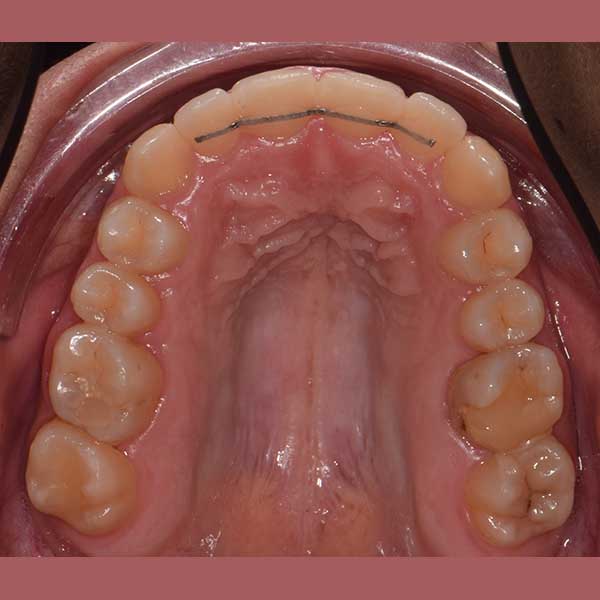

لحسن الحظ، وبعد دراسة الحالة، أكد الدكتور خالد الكاتب أن العلاج ممكن دون الحاجة للقلع. تم اختيار تقويم الدايمون (ذاتي الربط)، لما له من قدرة ممتازة على المساعدة في توسيع الفكين وتحريك الأسنان بفعالية لتوفير المسافة المطلوبة. سمحت هذه التقنية بحل الازدحام وإنزال الناب المرتفع إلى مكانه الصحيح.

النتيجة النهائية:

كما تظهر الصور، نجحنا في رصف الأسنان بشكل ممتاز وتحقيق إطباق مثالي. عاد الناب المرتفع إلى مكانه الطبيعي ضمن ابتسامة متناسقة وجميلة، مما أعاد لمراجعتنا الثقة والسعادة بابتسامتها.